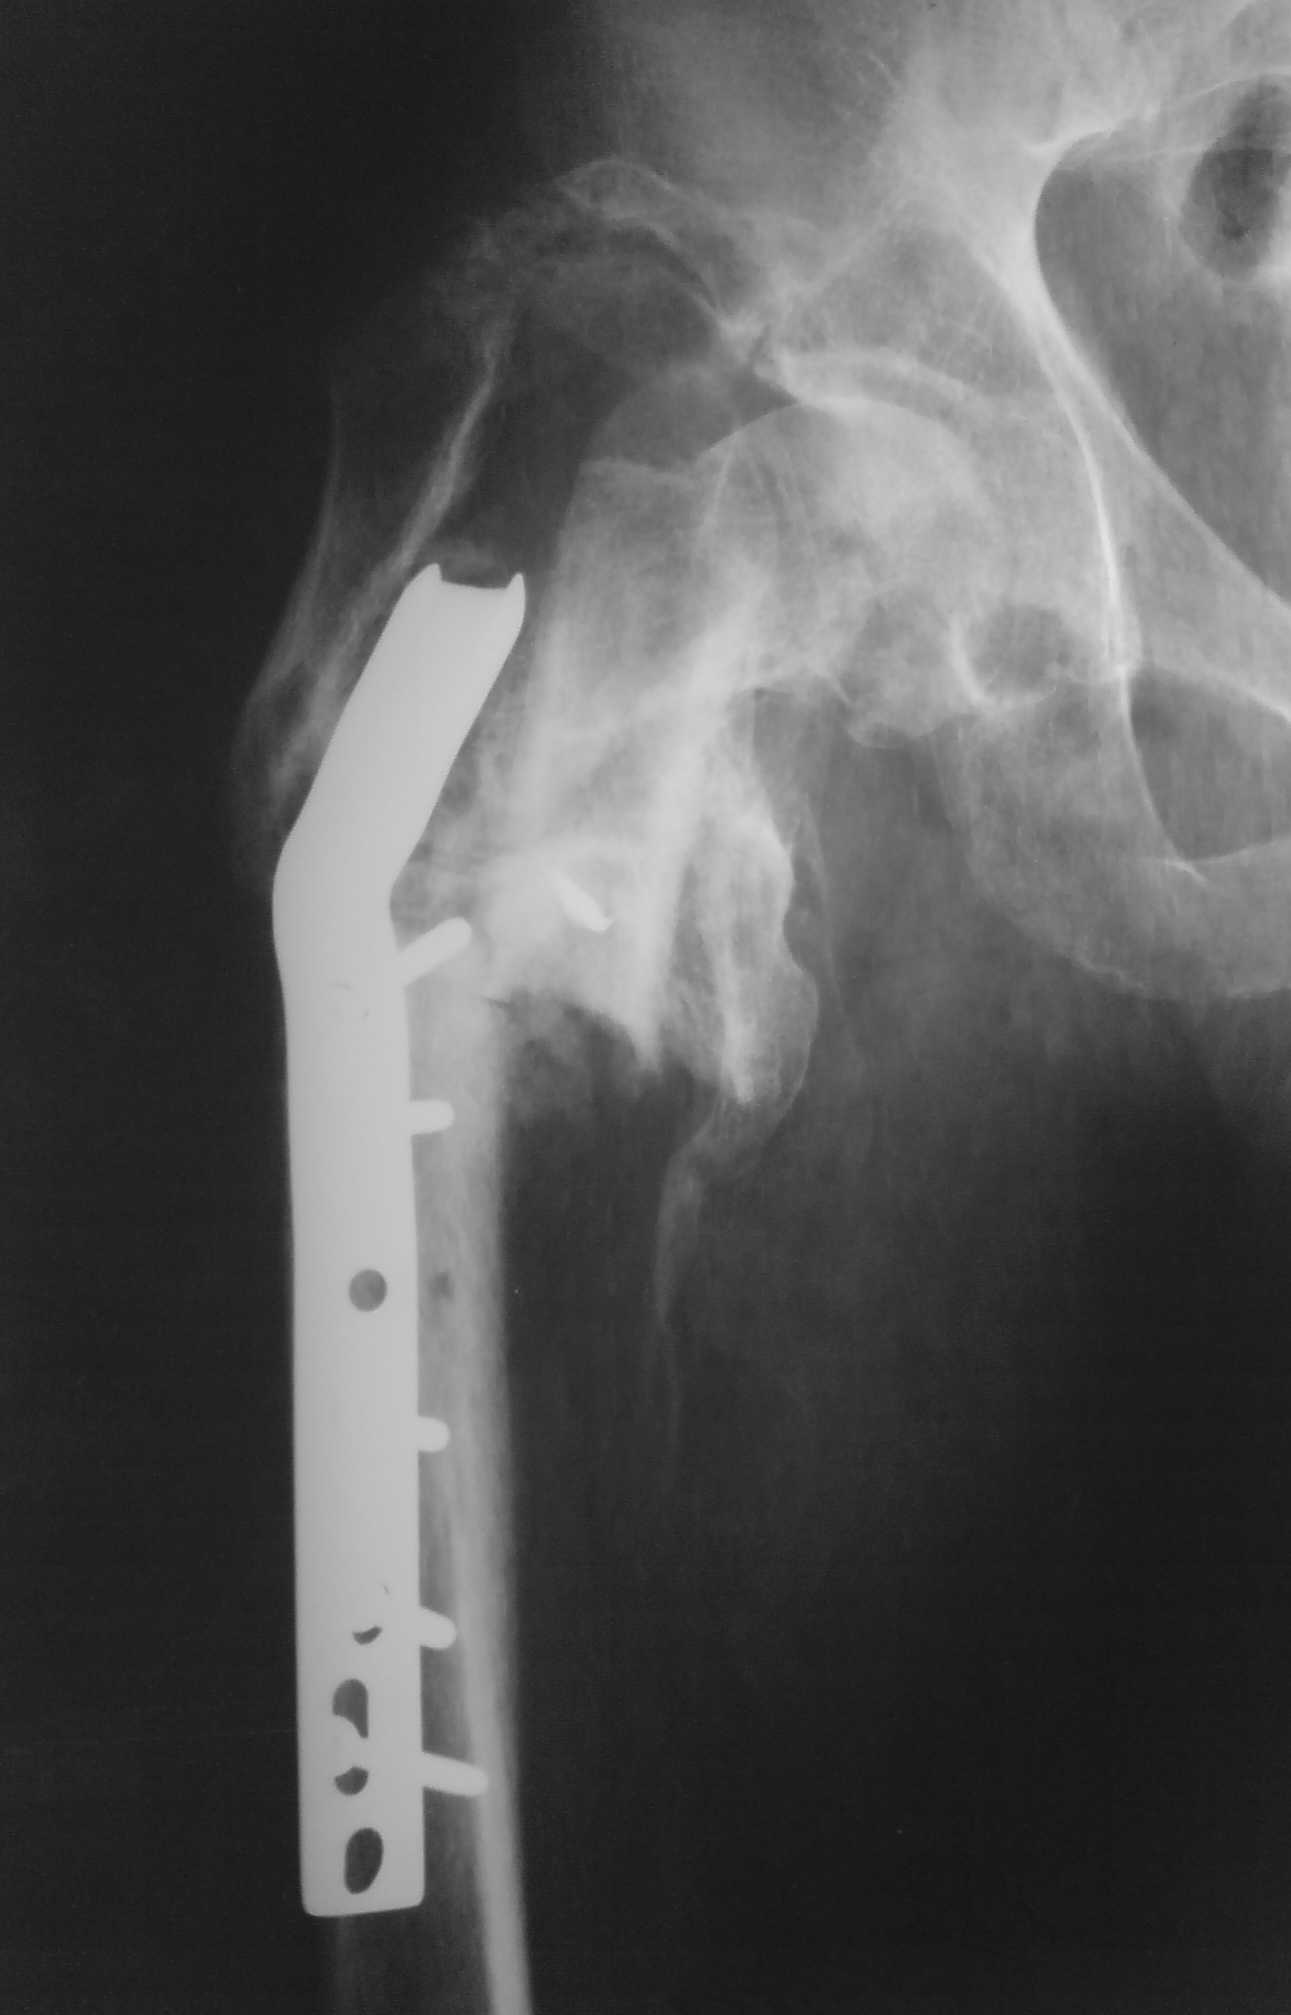

[Ortho] неправильно консолидированный перелом вертельной области (дополнение)

Имя     : DSC00409.JPG

Url     : http://weborto.net:8080/pipermail/ortho/attachments/20080325/cb38b33e/attachment-0002.jpeg